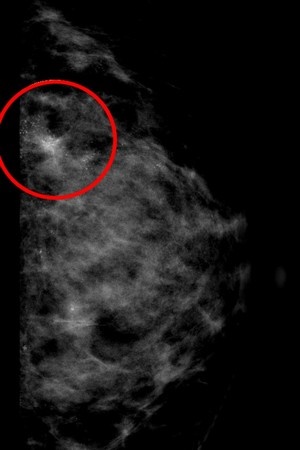

張群明主任說,乳房中的微小鈣化表現就如散沙一點一點散布或聚集在乳房中,在超音波上無法很明顯的照出來,得透過乳房攝影才能被發現,雖然乳房鈣化有八成為良性,但仍有少部分為惡性腫瘤的鈣化,需進一步取出乳房組織由病理科醫師判讀為良性還是惡性。

中、右圖:乳房醫學中心張群明主任說,乳房中的微小鈣化表現就如散沙一點一點散布或聚集在乳房中,在超音波上無法很明顯的照出來,得透過乳房攝影才能被發現。